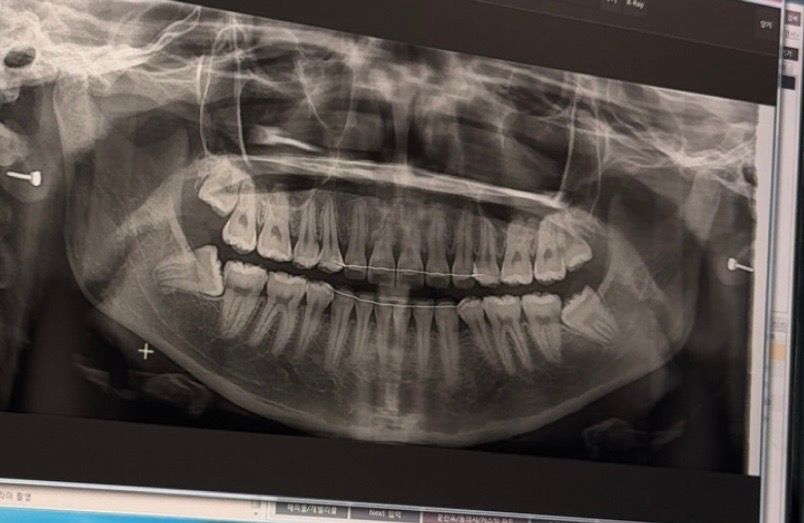

제가 6월 말에 미국 사관학교에 입학하는데, 학교 측에서 사랑니 발치를 추천했어요. 그런데 꼭 빼야 하는 건 아니라고 했습니다. 어제 구강외과에 가서 상담을 받았는데, 의사 선생님께서도 빼야 한다/안 빼도 된다를 명확히 말해주시지 않고 제 선택이라고 하셨어요. 저는 최대한 빼기 싫은데, 어떻게 하는 게 좋을까요? 참고로 한 번도 아픈 적은 없습니다.

부분매복 사랑니의 경우 앞으로 문제를 일으킬 가능성이 있고 미국의 경우 사랑니 발치 하나만 해도 비용이 비싸니 한국에서 하고 가는게 좋습니다